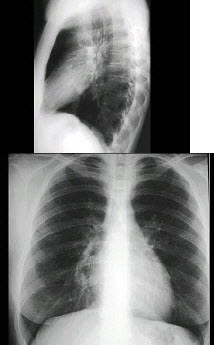

13、单项选择题

男,52岁,从事矿井工作32年,近几年出现气喘,呼吸困难,胸片如图,其最可能的诊断为()

A.双肺浸润性结核

B.双肺真菌感染

C.两肺弥漫性间质性肺炎

D.两肺弥漫性纤维化

E.矽肺